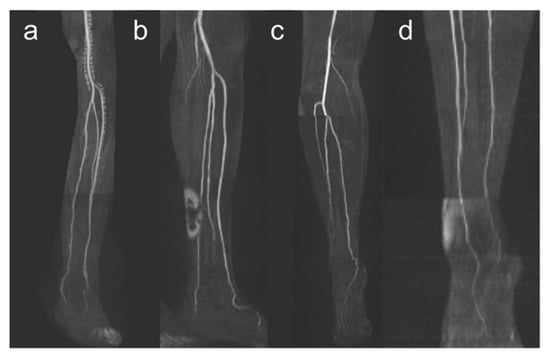

Figure 3.

Exemplary illustration of anatomical vessel variations of lower leg arteries. Panel (a) shows a type I-C according to Kim et al. [19] with the first exit of the PT below the knee joint with the subsequent exit of FA and AT via a common trunk. Panel (b) shows a hypoplastic PT (Type III-A) on the right side, and panel (c) shows a hypoplastic PT on both sides. Note the supply to the foot in these cases from the FA.